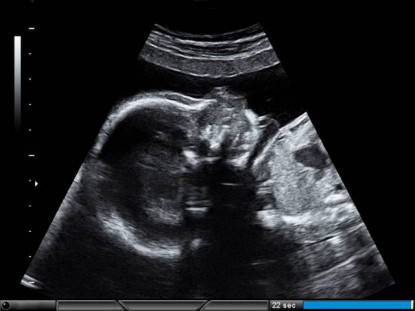

Quando si è incinte praticamente ogni mese si viene sottoposte ad un’ecografia.

Le più importanti sono le prime in cui si attesta se c’è battito e se la gravidanza prosegue regolarmente.

Non so voi unimamme in attesa o meno, ma io quando guardavo nell’ecografo non capivo assolutamente niente: a parte la colonna vertebrale, che era perfettamente chiara, né io né mio marito capivano se stessimo di fronte ad un piede, un occhio, un pezzo d’orecchio e al cervello.